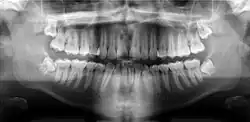

Once a person is having symptoms related to Gigantiform cementoma it is suggest to seek medical attention. The health providers that can help would be a Dentist, Oral Surgeon, Oral Pathologist, and Prosthodontist. A dentist can do an exam and take x-rays to evaluate symptoms and to be able to refer the patient to the correct specialist. An Oral Surgeon are specialized with surgical procedures related to the mouth, jaw and the face. An Oral Pathologist is able to help with diagnosis by examining the tissues samples in order to diagnosis and treat diseases related the jaw, and mouth. Prosthodontist are able to aid with the missing teeth. The doctors specialize with dental prosthetics. In order to diagnosis a patient with Gigantiform cementom there has to be X-ray done that provides the doctor with the view of the jaw and the teeth to identify the tumor and to also be able to see the size of the tumor. There are different types of X-rays that can be done which are the Panoramic Radiograph and Cone Beam Computed Tomography (CBCT). Biopsy may be suggested by an Oral Surgeon to be able to collect tissues from the tumor to get samples for histological examine, this is necessary to confirm diagnosis. Blood test can also be done to confirm diagnosis.